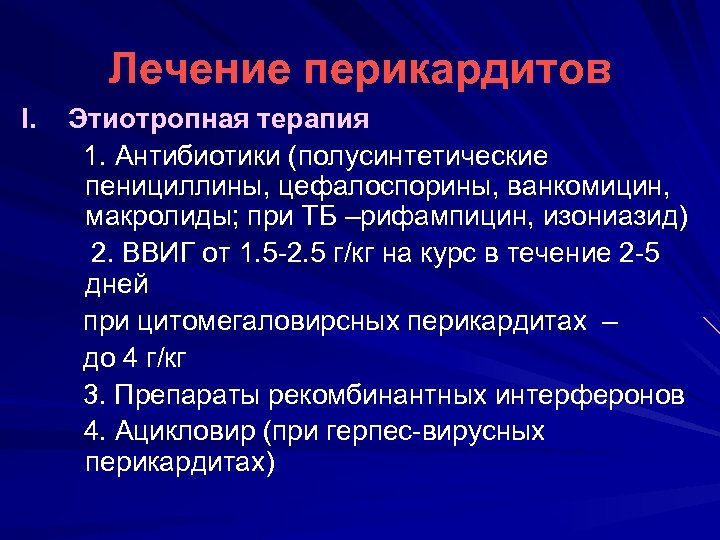

Лечение перикардитов I. Этиотропная терапия 1. Антибиотики (полусинтетические пенициллины, цефалоспорины, ванкомицин, макролиды; при ТБ –рифампицин, изониазид) 2. ВВИГ от 1. 5 -2. 5 г/кг на курс в течение 2 -5 дней при цитомегаловирсных перикардитах – до 4 г/кг 3. Препараты рекомбинантных интерферонов 4. Ацикловир (при герпес-вирусных перикардитах)